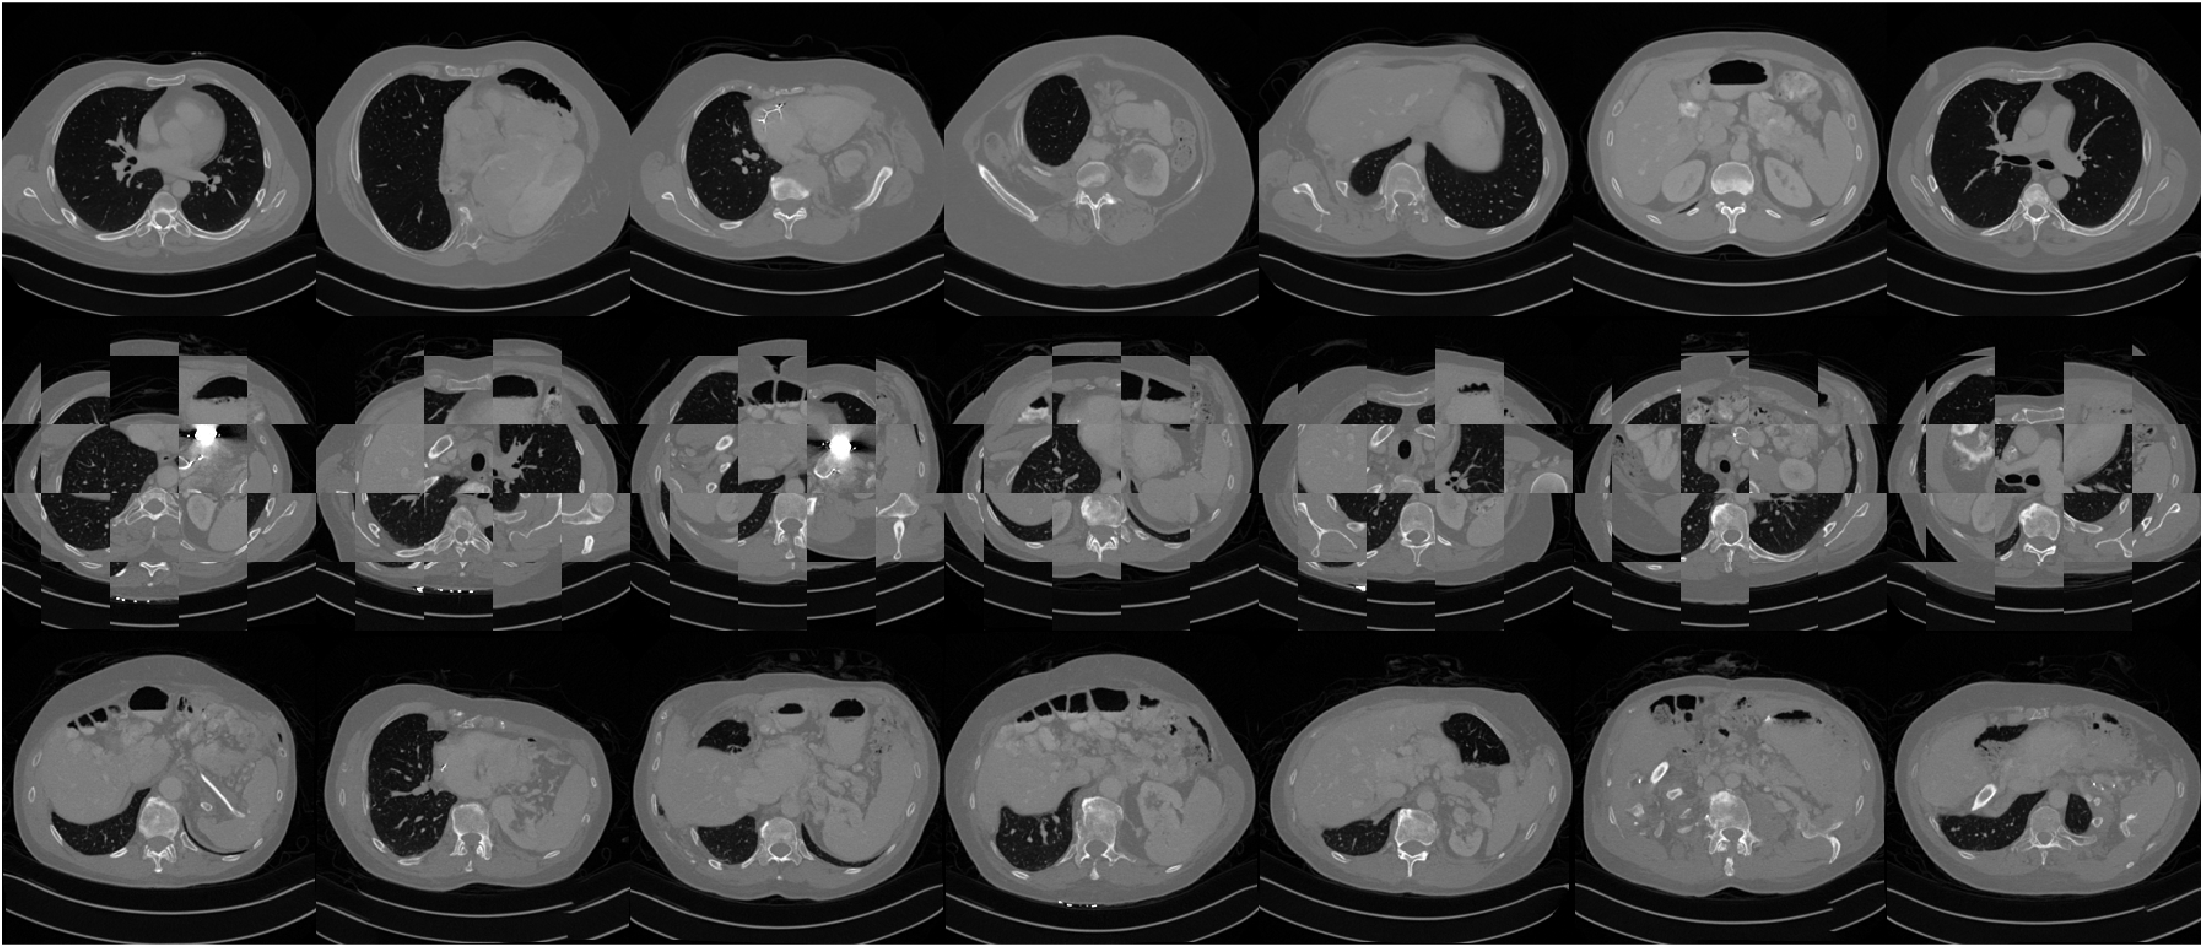

Effect of training dataset size.

A key motivation of this work is large-scale inverse problems having limited training data. To investigate the effects of using small datasets on our proposed method, compared to standard whole image models, we trained networks on random subsets of the CT dataset. Table 5 summarizes the results. Crucially, although the reconstruction quality tends to drop as the dataset size decreased for both the patch-based model and the whole image model, the drop is much more sharp and noticeable for the whole image model, particularly when the dataset is very small. This behavior is consistent with the observations of previous works where large datasets consisting of many thousands of images were used to train traditional diffusion models from scratch.

Figure A.5 shows the results of applying PaDIS to two example test images with different patch sizes. The main results, i.e., those shown in Table 1, used P=56P=56. For some of the other patch sizes, some artifacts can be seen in the images. Namely, the smooth parts of the image become riddled with "fake" features for small patch sizes and some of the sharp features become more blurred. The fake features in the right half of the image in the top row are especially apparent when applying the whole-image model. The runtime for different patch sizes were fairly similar, with P=8P=8 taking notably longer than the others due to the large number of patches required. The image size for these experiments was small enough so that the score function of all the patches could be computed in parallel; however, for larger scale problems such as high resolution 2D images or 3D images, large patch sizes become infeasible due to memory constraints.

Figure A.6 shows the results of applying our proposed method and the whole image diffusion model to 20-view CT reconstruction for varying sizes of the training dataset. The image quality for PaDIS remains visually consistent as the size of the training dataset shrinks, as each image contains thousands of patches which helps avoid overfitting and memorization. However, the drop in quality for the whole image model is much more visible: in particular, the sharp features of the image are lost and the image becomes blurry. Hence, for applications where data is even more limited, such as medical imaging, our method can potentially have a greater benefit.

Refer to caption

Figure A.6: Results for 20 view CT reconstruction with different dataset sizes. Top row shows recon performed by PaDIS; bottom row shows recon performed with the whole-image model.